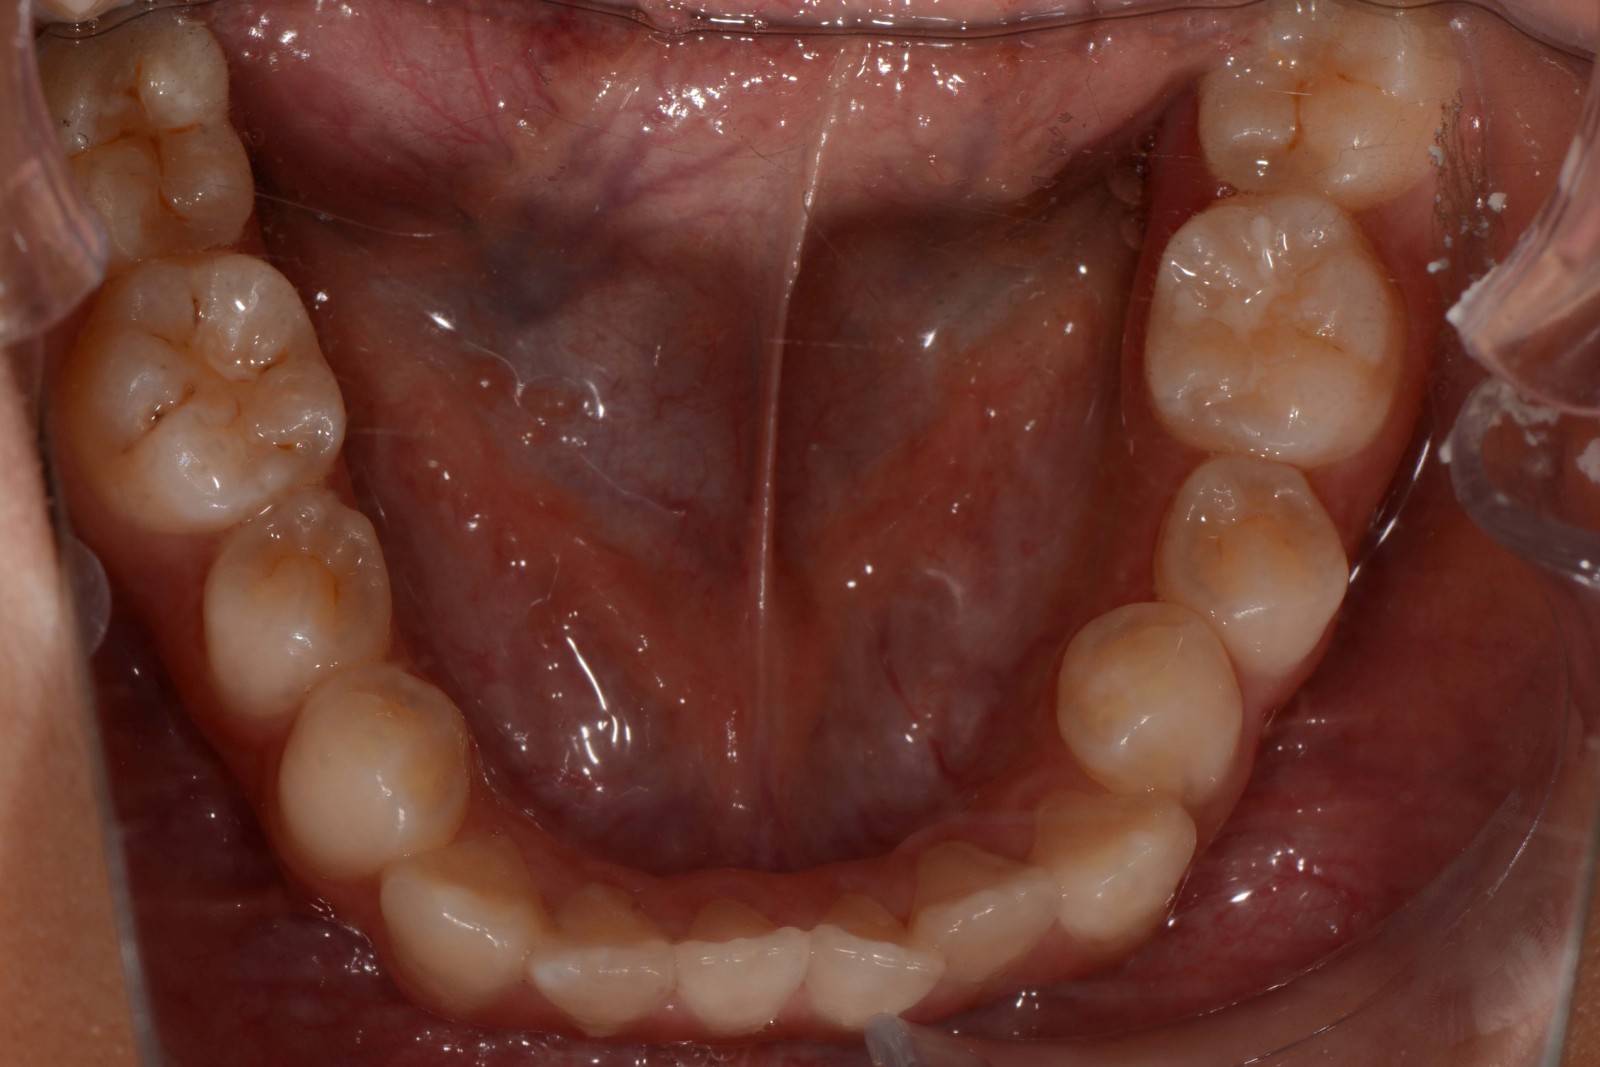

患者:14岁女性

前牙区开颌3mm

诊断:安氏II类错颌畸形  开颌

矫治后: